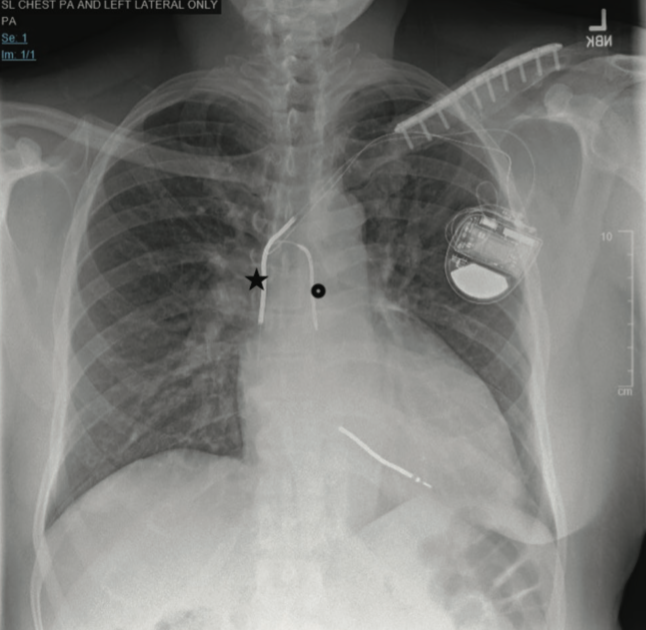

Azygos Lead Implantation in a Patient with High Defibrillation Thresholds: Case Report and Brief Review

Implantable cardioverter-defibrillators (ICDs) are the cornerstone therapy for terminating life-threatening ventricular arrhythmias, which are a common cause of sudden cardiac death.1

Routine defibrillation threshold (DFT) testing is somewhat controversial. There are several causes of elevated DFTs necessitating testing, which include patient-specific factors (ie, metabolic abnormalities, ischemic heart disease), implant-related issues, device type, medications, electrolytes, sympathetic tone, and antiarrhythmic medications.2,3 In the rare occurrence that an individual has an elevated DFT, it poses a challenge on the effectiveness of therapy delivered by an ICD.4